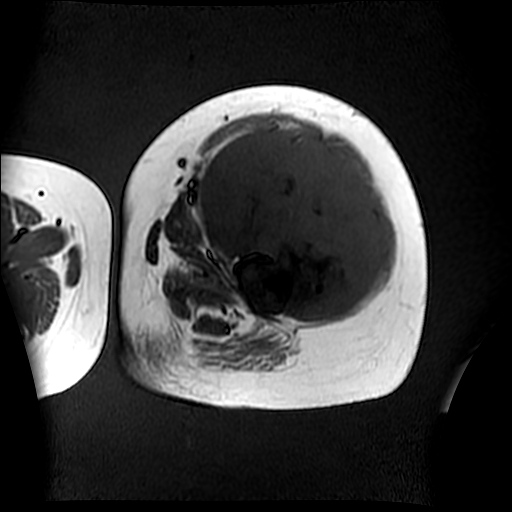

左侧大腿外伤10余年,当时情况不清,发现左侧大腿肿胀7年余,而后又有多次外伤史,近1年来出现疼痛,减重半年。查体:左侧大腿肿胀明显,皮温、肤色正常。

软组织肿块,股骨破坏,增强不均匀强化-----支持恶性肿瘤